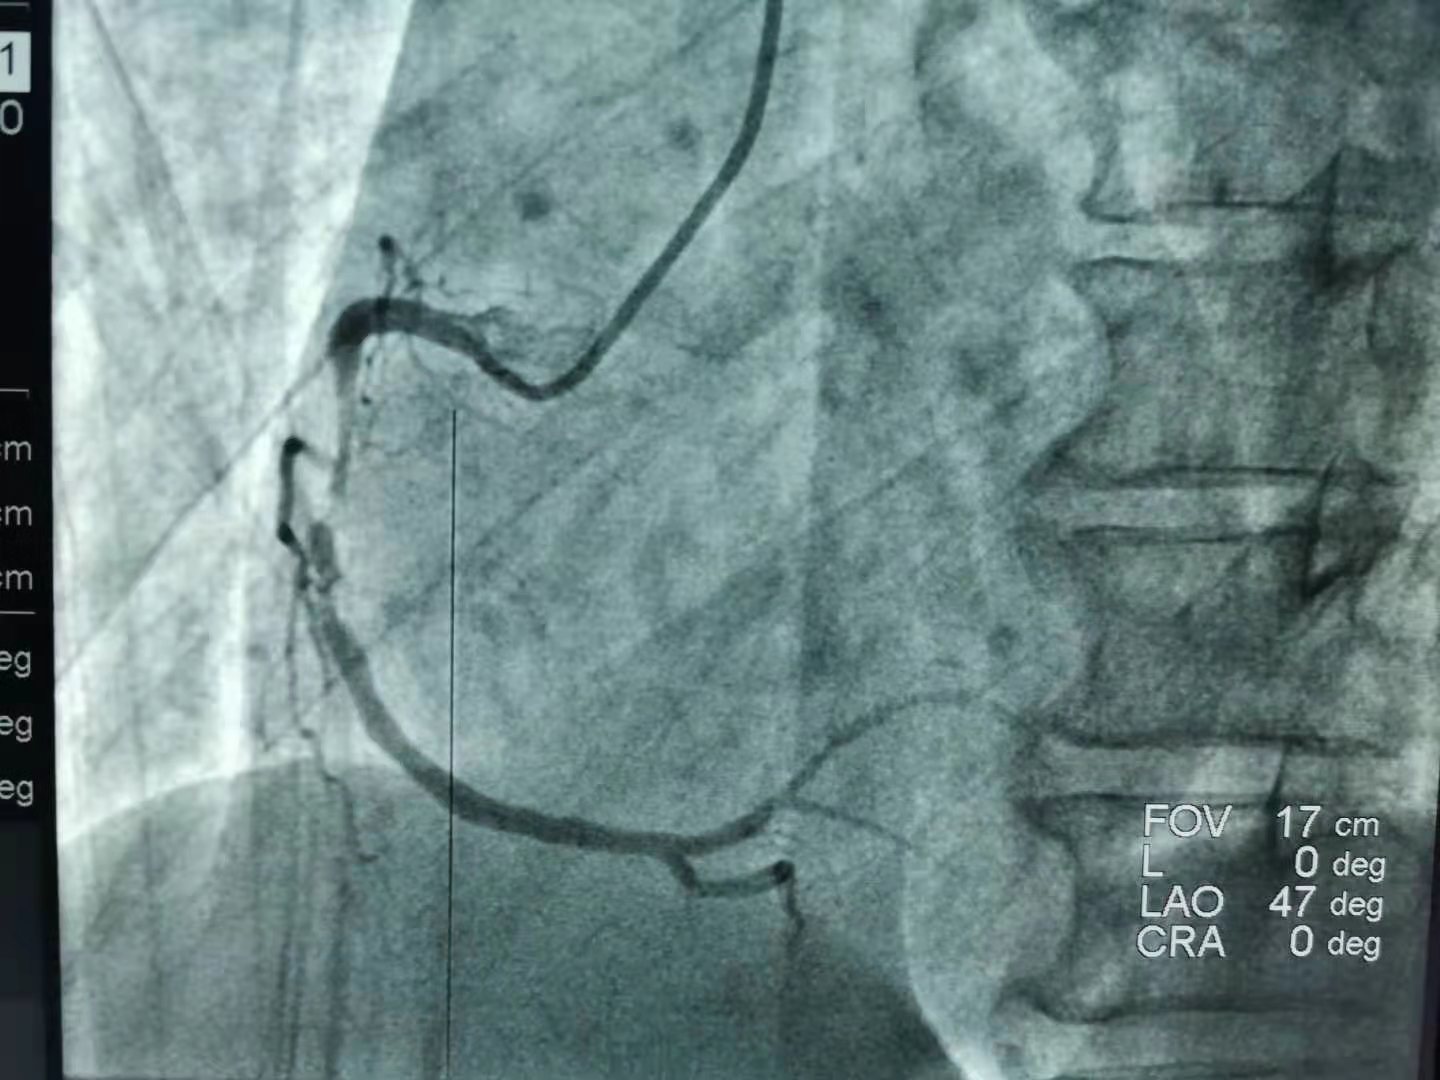

18:20“一键启动导管室”!18:35李先生到达导管室开始手术。“冠状动脉造影显示,李先生右冠状动脉近端99%的严重狭窄,需要立即植入支架!”在介绍救治方案并征得家属的同意后,副院长张施明带领胸痛中心手术团队对患者进行支架植入手术,18:53导丝通过,19:08 在距离李先生发病68分钟后,手术顺利完成,李先生转危为安。

李先生的术前术后对比,可见右冠状动脉严重狭窄处已再通,冠状动脉粗壮可见